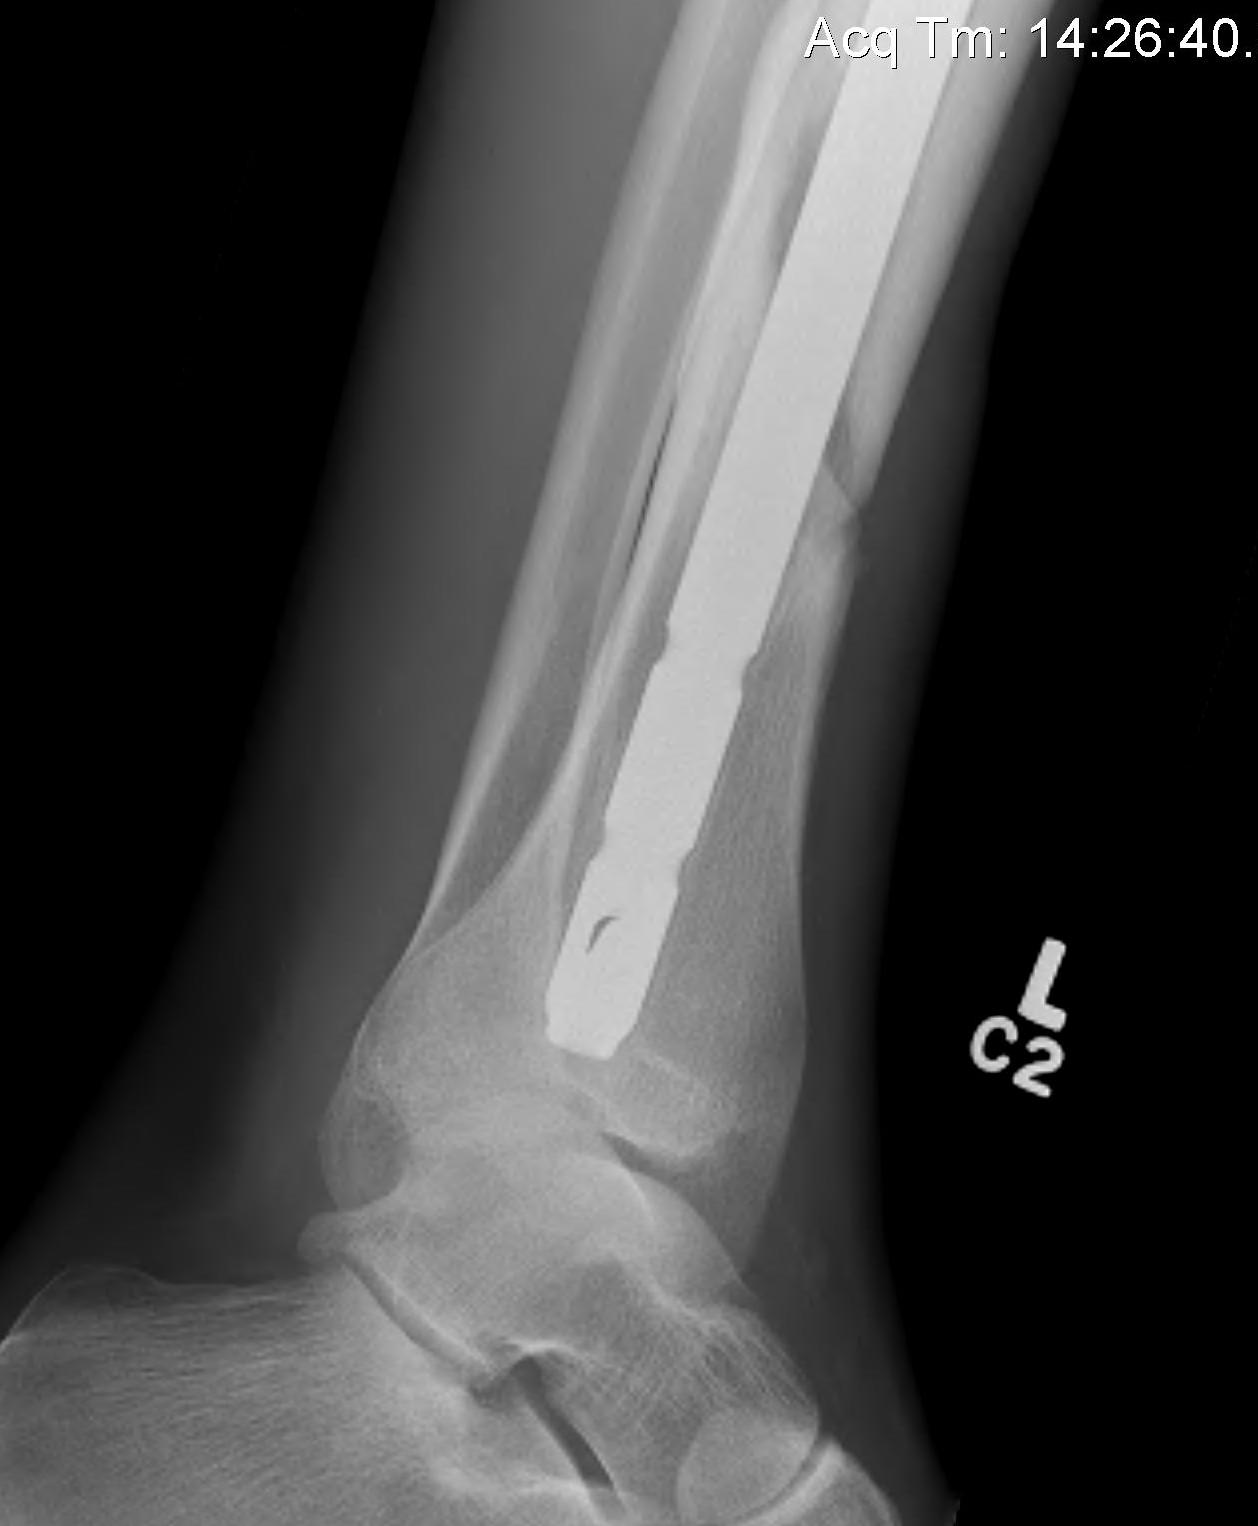

- occult in 70%

- especially with spiral distal tibial fractures

Wang et al. J Orthop Surg Res 2021

- systematic review

- incidence 70% occult fractures